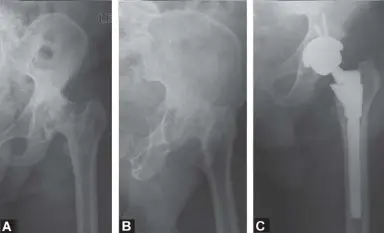

يُعد استبدال مفصل الورك الكلي (Total Hip Replacement - THR) إحدى أنجح العمليات الجراحية في مجال جراحة العظام، وقد لُقبت بحق بـ "عملية القرن العشرين" نظرًا لتأثيرها التحويلي على جودة حياة المرضى وفعاليتها من حيث التكلفة. ومع ذلك، فإن نجاح هذه العملية لا يعتمد فقط على مهارة الجراح أثناء التدخل، بل يبدأ قبل ذلك بكثير: بالتخطيط المسبق الدقيق والشامل.

يُعد التهاب المفاصل التنكسي، المعروف أيضًا بالخشونة، السبب الأكثر شيوعًا لألم الورك الذي يتطلب الاستبدال. يحدث هذا عندما يتآكل الغضروف الواقي الذي يغطي نهايات العظام تدريجيًا، مما يؤدي إلى احتكاك العظام ببعضها البعض، مسببًا الألم والتصلب ومحدودية الحركة.

النخر اللاوعائي (Avascular Necrosis - AVN)

يحدث النخر اللاوعائي عندما ينقطع تدفق الدم إلى رأس عظم الفخذ، مما يؤدي إلى موت الأنسجة العظمية وانهيارها. يمكن أن يحدث هذا بسبب إصابة، أو استخدام الكورتيكوستيرويدات لفترات طويلة، أو الإفراط في تناول الكحول، أو بعض الأمراض المزمنة.

كسور الورك

قد تؤدي كسور الورك الشديدة، خاصة تلك التي تؤثر على رأس عظم الفخذ، إلى تلف لا يمكن إصلاحه للمفصل، مما يستدعي استبداله.

تشوهات الورك الخلقية أو النمائية

- خلل التنسج الوركي (Hip Dysplasia): حالة لا يتشكل فيها مفصل الورك بشكل صحيح عند الولادة أو أثناء النمو.

- مرض بيرثيس (Perthes Disease): حالة نادرة تصيب الأطفال، حيث ينقطع تدفق الدم إلى رأس عظم الفخذ، مما يؤدي إلى تليينه وانهياره.

- انزلاق المشاش الفخذي الرأسي (Slipped Capital Femoral Epiphysis - SCFE): حالة تحدث في المراهقة حيث ينزلق رأس عظم الفخذ من صفيحة النمو.